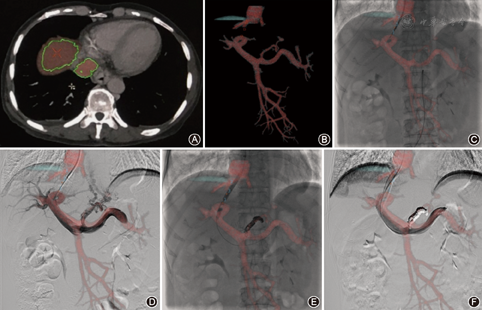

将患者术前的CT原始数据采用刻录光盘的方式导入GE AW工作站,重建三维图像,需要在门静脉三维图像生成膈顶、肝顶,大量腹水时,标记穿刺靶点、路径(图1)。输出在"Film/Save"栏中通过"Save State"保存处理好的三维图像或依次单击"Innova Export"、"Export"直接输出到实时手术图像上。输出后可分别显示三维骨像、门静脉像,在转动C臂、变化视野及移动床时,三维图像均实时变化。

匹配首先在正位及侧位透视模式下应用三维骨像(以第11胸椎为中心)进行正侧位对位首次匹配。之后切换为门静脉血管像。间接门静脉造影后精确二次匹配影像融合图像与DSA。利用"3D Model Opacity"调节三维图像透明度,以利于术中实时观察二维图像。将匹配好的门静脉图像作为路径图,利用虚拟穿刺路径功能向门静脉靶点穿刺,后续同常规TIPS操作[7]。

纵向误差1.7~2.5(2.1±0.2)mm,横向误差0.9~1.8(1.4±0.3)mm。纵向误差小18例(85.7%),纵向误差一般2例(9.5%),纵向误差较大1例(4.8%);横向误差小20例(95.2%),横向误差一般1例(4.8%),横向误差较大0例(0%)。